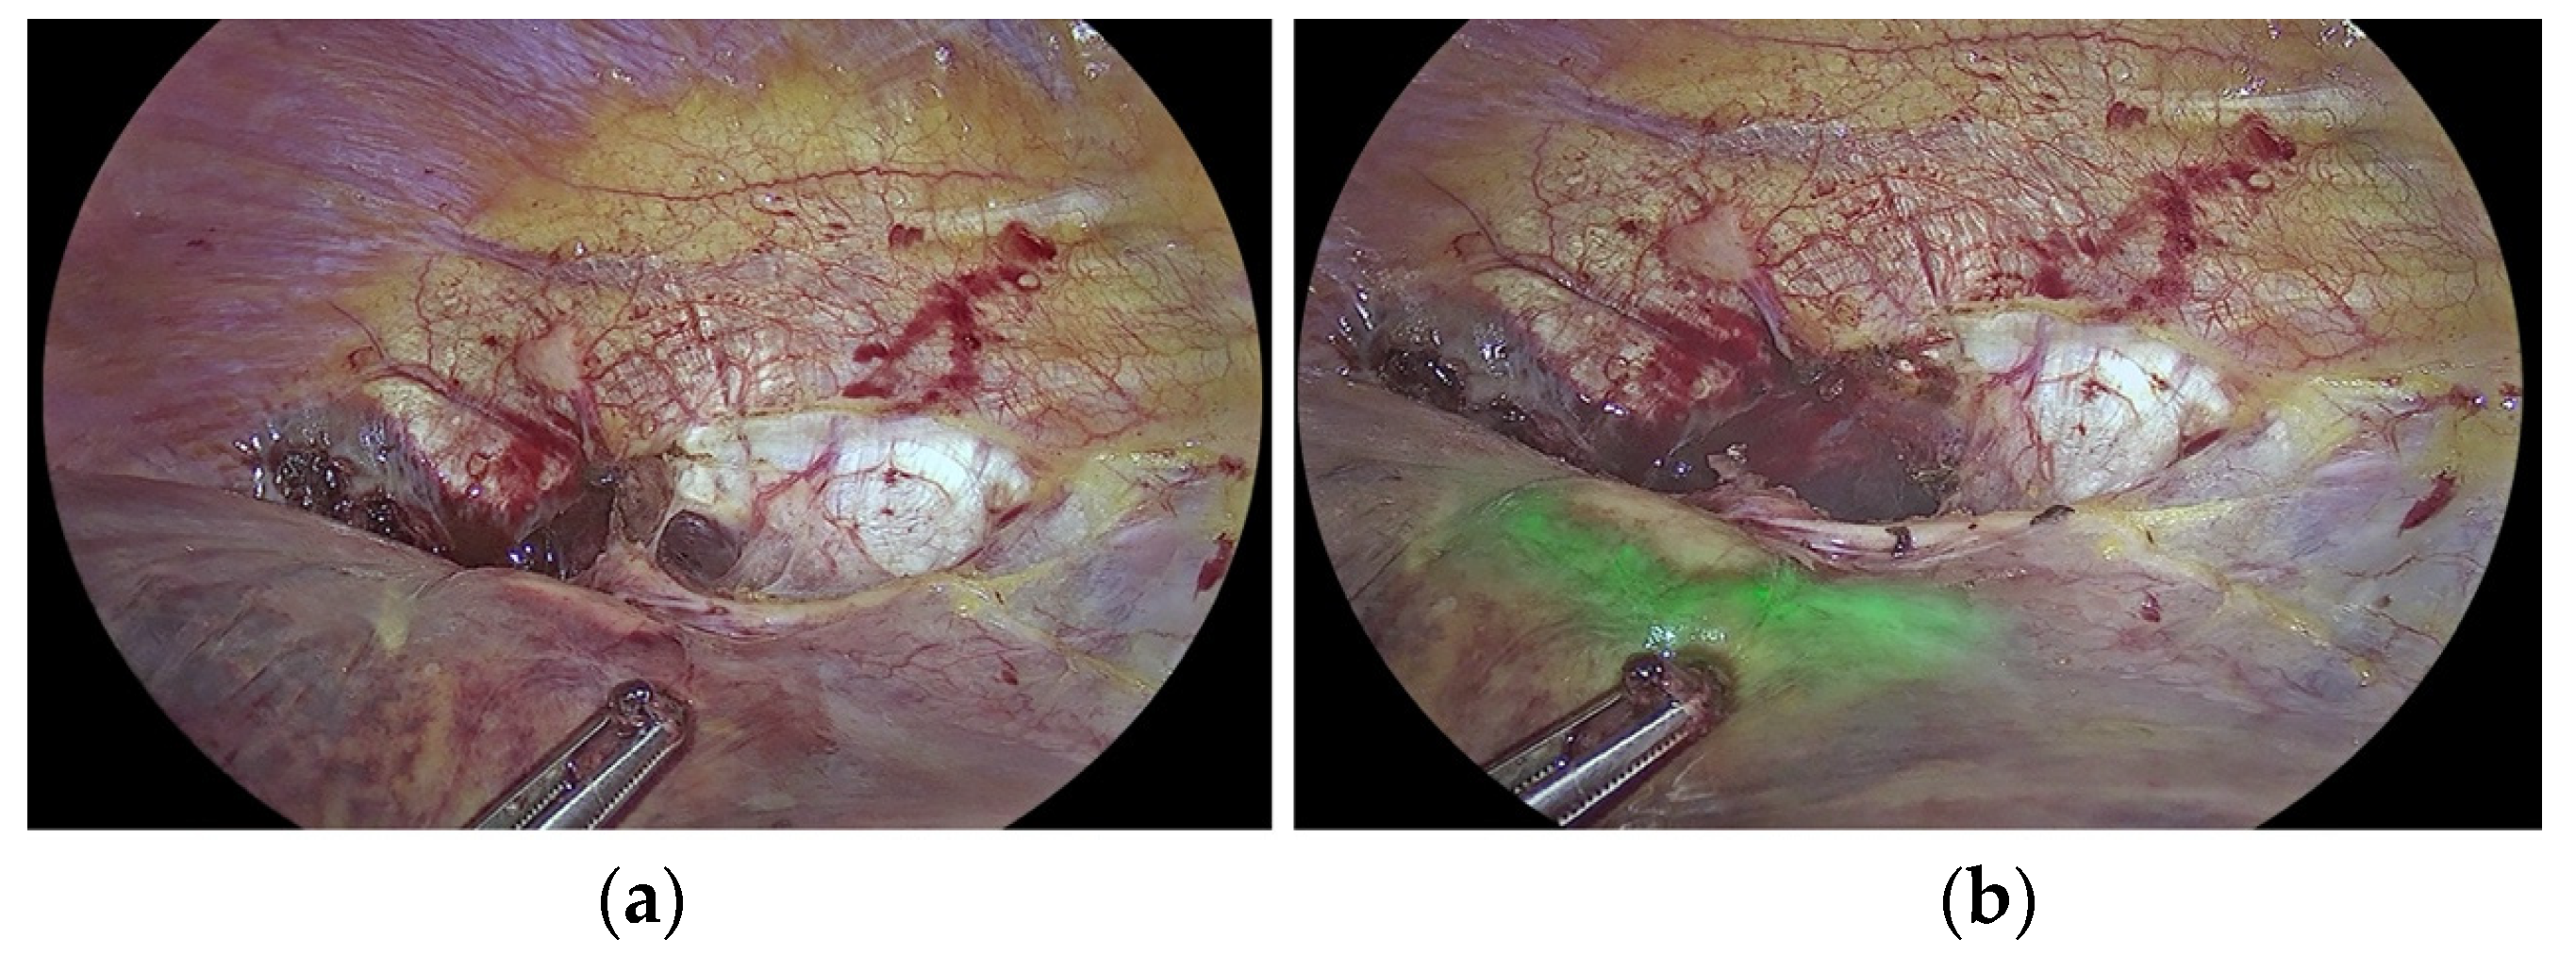

- Raimondo, D.; Maletta, M.; Malzoni, M.; Cosentino, F.; Scambia, G.; Falcone, F.; Coppola, M.; Turco, L.C.; Borghese, G.; Raffone, A.; et al. Indocyanine green fluorescence angiography after full-thickness bowel resection for rectosigmoid endometriosis: A multicentric experience with quantitative analysis. Int. J. Gynecol. Obstet. 2021, 158, 679–688. [Google Scholar] [CrossRef]